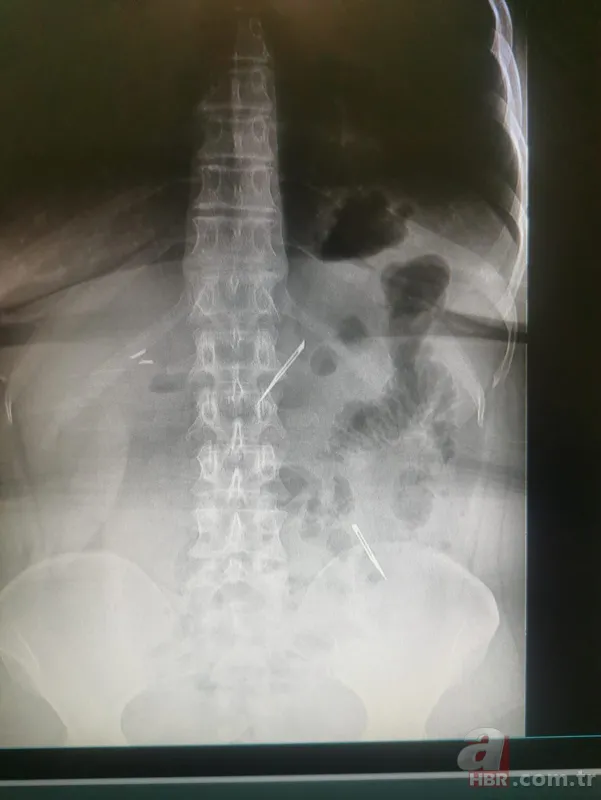

Amasya Üniversitesi Sabuncuoğlu Şerefeddin Eğitim ve Araştırma Hastanesi'ne başvuran G.D.'nin yapılan tetkik ve tahlillerinde karnında büyük bir kitle olduğu belirlendi. İki saat süren ameliyatla hastanın karnındaki yaklaşık 5 kiloluk kitle alındı.

Ekibiyle birlikte operasyonu gerçekleştiren Kadın Hastalıkları ve Doğum Uzmanı Prof. Dr. Osman Fadıl Kara, "Hastamızda geldiğinde kaburga altına kadar büyüyen 7 aylık gebelik gibi görünen bir kitle olduğunu fark ettik. Operasyonda karnı açtığımızda yaklaşık 5 kiloluk bir kitle olduğunu görüp çıkardık. Şu an hastamızın durumu iyi" diye konuştu.